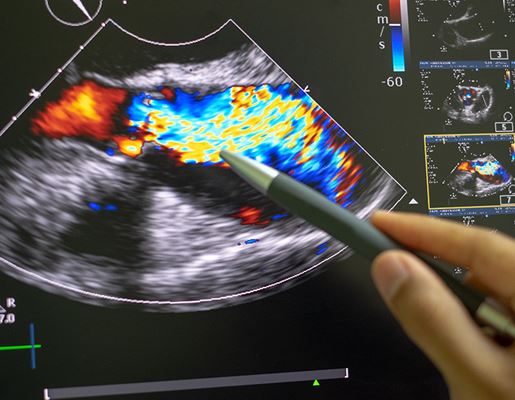

- Echocardiogram – to check how well the heart valves are working